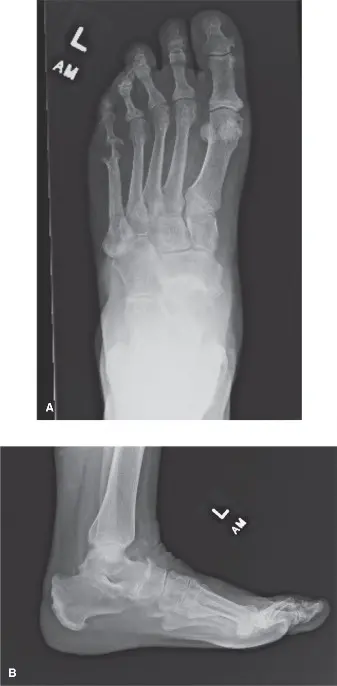

• التشخيص: يعتمد على الفحص السريري وصور الأشعة السينية التي تظهر تضيقًا في الفراغ المفصلي وتكون نتوءات عظمية. قد يكون التصوير بالرنين المغناطيسي (MRI) أو الأشعة المقطعية (CT) ضروريًا لتقييم مدى تلف الغضروف.

كسور الإجهاد في عظم الكعب

كسور الإجهاد في عظم الكعب (Calcaneal Stress Fracture) هي شقوق صغيرة تتطور في عظم الكعب نتيجة الإجهاد المتكرر، وليس صدمة واحدة. شائعة لدى العدائين، المجندين العسكريين، والأشخاص الذين يعانون من ضعف في كثافة العظام.

• الأعراض: ألم تدريجي في الكعب، يزداد سوءًا مع النشاط ويتحسن مع الراحة. قد يكون هناك تورم أو كدمات.